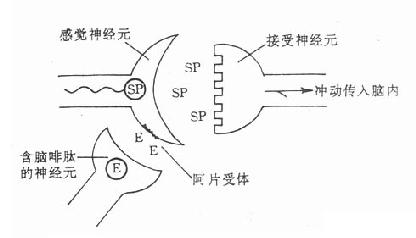

图18-2含脑啡肽的神经元与疼痛

疼痛刺激使感觉神经末梢兴奋并释放兴奋性递质(可能为P物质),

该递质与接受神经元上的受体结合,将痛觉冲动传入脑内.感觉神经元末梢上

存在阿片受体,含脑啡肽的神经元释放脑啡肽,后者与阿片受体结合,

减少感觉神经末梢释放P物质,从而防止痛觉冲动传入脑内.E:脑啡肽;SP:P物质

【作用机制】现有资料证明,在体内存在有“抗痛系统”,它由脑啡肽神经元、脑啡肽及阿片受体共同组成。去极化或刺激脑啡肽神经通路可引起脑啡肽释放,并依赖于钙离子。在正常情况下约有20%~30%的阿片受体与脑啡肽结合,起着疼痛感觉的调控作用,维持正常痛阈,发挥生理性止痛机能,镇痛药的作用是激动阿片受体,激活了脑内“抗痛系统”,阻断痛觉传导,产生中枢性镇痛作用。

阿片受体的发现提示脑内可能存在相应的内源性阿片样活性物质,不久即自脑内分离出两种五肽,即甲硫氨酸脑啡肽(M-enkephalin)和亮氨酸脑啡肽(L-enkephalin),它们在脑内的分布与阿片受体的分布近似,并能与阿片受体呈立体特异性结合而产生吗啡样作用,这种作用可被吗啡拮抗药纳洛酮所拮抗。继发现脑啡肽之后,又自垂体中分离出几种较大的肽类,称为内啡肽(endorphins),如β-内啡肽(β-endorphin)及强啡肽(dynorphin A)。迄今已发现近20种作用与阿片生物碱相似的肽类,统称为内阿片样肽(或内阿片肽)。内阿片肽可能是神经递质或神经调质(即调节神经递质释放的物质)或神经激素,在机体内起着痛觉感受的调控或内源性镇痛系统以及调节心血管及胃肠功能的作用,例如在脊髓感觉神经末梢已发现阿片受体,实验资料提示脑啡肽可能通过抑制感觉神经末梢释放一种兴奋性递质(P物质),从而干扰痛觉冲动传入中枢(图18-2)。至于吗啡类药物的作用机制则可能是通过与不同脑区的阿片受体结合,模拟内阿片肽而发挥作用的。